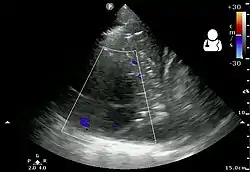

The initial investigations for suspected empyema remains chest X-ray, although it cannot differentiate an empyema from uninfected parapneumonic effusion.[5] Ultrasound must be used to confirm the presence of a pleural fluid collection and can be used to estimate the size of the effusion, differentiate between free and loculated pleural fluid and guide thoracocentesis if necessary. Chest CT and MRI do not provide additional information in most cases and should therefore not be performed routinely.[6] On a CT scan, empyema fluid most often has a radiodensity of about 0-20 Hounsfield units (HU),[7] but gets over 30 HU when becoming more thickened with time.[8]

- 1 2 3 4 "UOTW #28 - Ultrasound of the Week". Ultrasound of the Week. 3 December 2014. Archived from the original on 9 May 2017. Retrieved 27 May 2017.